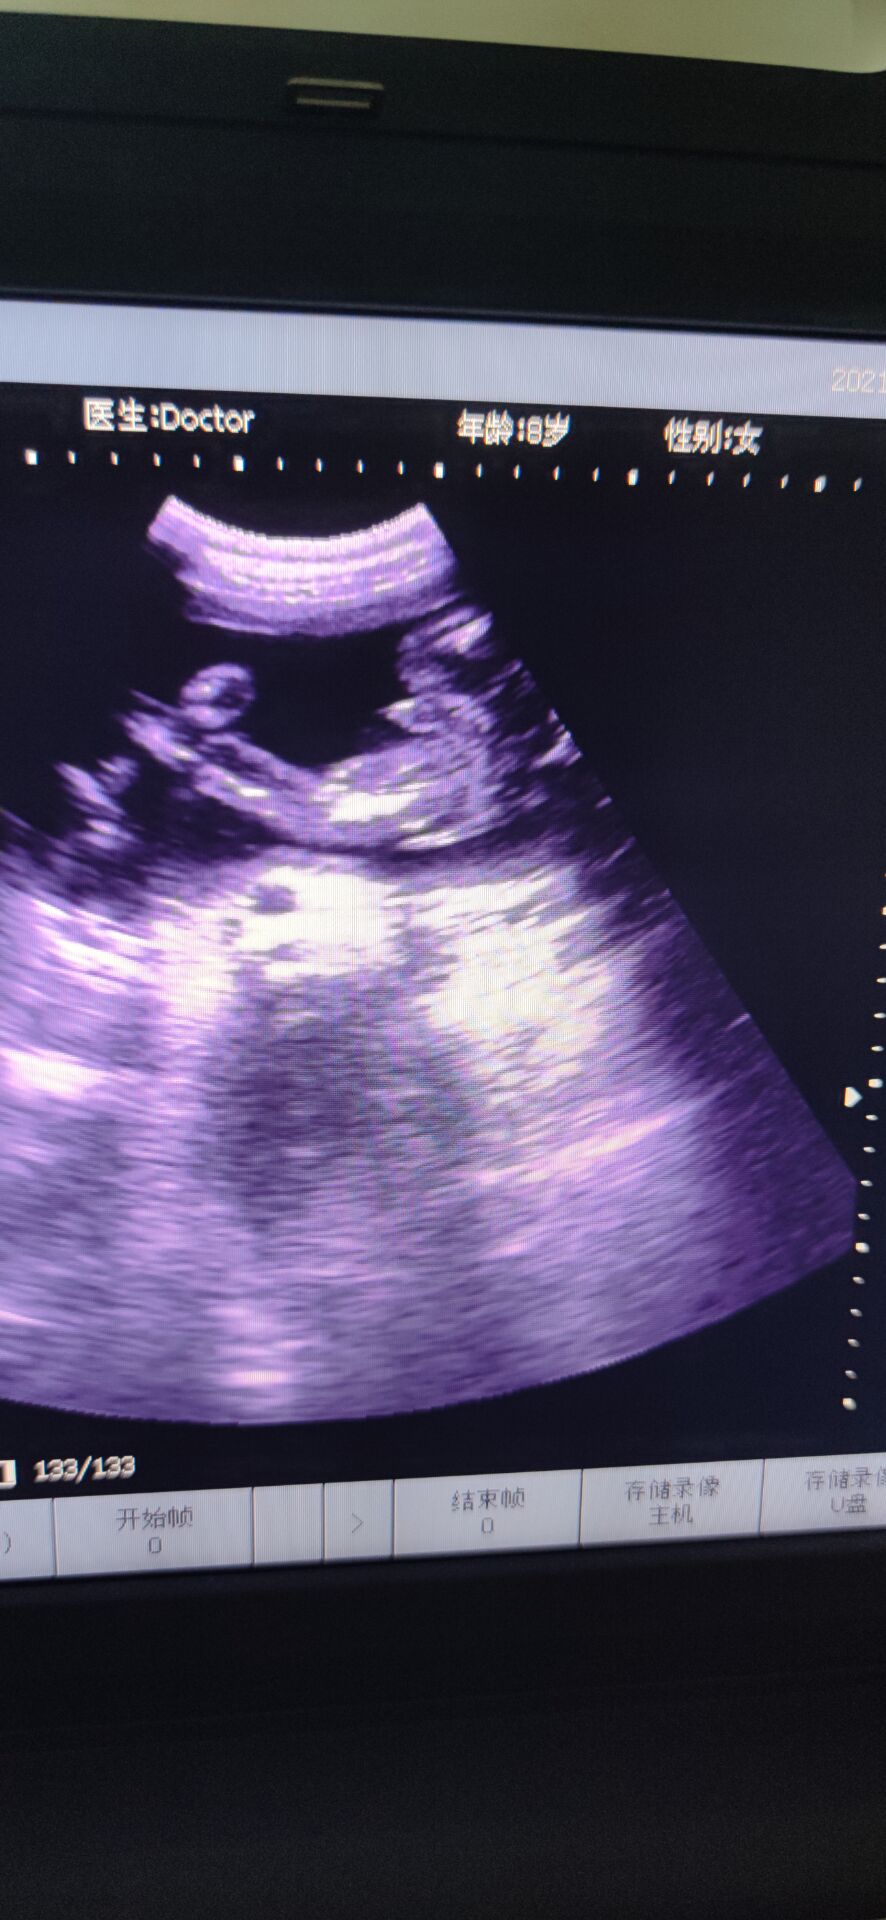

6月5日下午,分泌物有点血丝,而我在洗碗的时候,小腹有点点坠痛,但是休息下能缓解,到了晚上跟孕妇群的人聊了聊,不放心,挂急诊,B超做了好久,突然医生让我别动,就躺着,说:“你宫口已经开了,内宫口全开了,外宫口开了两指了,羊膜在阴道里,都快到阴道口了!”听到的那刻,突然就心慌紧张了,整个人都在发抖,腿也控制不住地抖,才26周啊,还没足月。产科的人立马下来把我拉到待产室内检,然后跟我说还没足月,什么都还没发育好,生下来就要立马进保温箱,要生下来起码得准备一百万…说了很多,大概意思都是劝我引产,可是我舍不得啊,我下不定决心,她们就破例让我老公进来,同样地话跟我老公说了一遍,但是我们想保,医生就给了建议,转入市人民医院,那里有紧急环扎术,当天晚上就转过去,中途医生给我上了抑制宫缩的药。转过去的时候已经是凌晨两点多了,医生说她们医院已经不做紧急环扎术了,她也不知道哪个医院能做,而且这么晚了,我再转院也是折腾,我这才26周,产科和妇科不会收的,只能收计划生育科,但是计划生育科是不会管我的,因为我这情况医学上说就是难免流产,打完从上一个医院带来的吊瓶后,是不会管我的,顺其自然。这不是我们想要的答案,医生说没有其他办法,我们也不知道该怎么办,想着先转计划生育科吧,当晚做的核酸,但是因为核酸报告没那么快出,所以把我放到了抢救室,期间打了一枚促肺针。那晚好煎熬啊,睡又睡不着,周围都是打吊瓶的人,临急出的门,手机又没什么电,又不敢乱动,躺的身子僵硬疼痛,又不能下床走动,老公给我买了包护理垫,上厕所就直接尿在护理垫上。好不容易熬到早上,核酸报告还没出,到了十点多也没出,我老公在网上查资料,打电话,看哪个医院可以做紧急环扎,他侧对着我坐着,我看到他哭了,默默在流泪,那时候真心疼他。好不容易市妇幼说她们医院可以做,但是不派车来接,人民医院也不派车送。怎么办呢,叫出租车吗?可是出租车会愿意拉我吗而且我还得躺着。我老公和我家公就出去联系私人救护车。出去了好久,我就躺在床上望着门口,一有人进来,我就以为是他们回来了,但是不是,是别的病人的家属,后来我借别人手机给他打电话,我说:“你不要离开太久,我一个人在这,我害怕[泣不成声]”我老公他们好不容易联系到私人救护车把我送到市妇幼,内检时医生说做不了紧急环扎了,我已经有宫缩了,只能打吊瓶,抑制宫缩。因为疫情原因,只能一个陪护,我老公做的核酸还没出报告,要明天才能出,所以临时请了个月嫂陪护我,那天已经是6月6日了,晚上睡觉的时候感觉尿尿那里湿湿的,一擦,有血丝,而且不是一点点,叫了医生,医生给我上了另一种抑制宫缩的药,没一会就心跳加速,医生说那药是会让心跳加速,还让我如果有宫缩要告诉她。那一整晚都睡不安稳,一整晚,时间才过去五分钟,感觉太难熬了。等到6月7日中午,我老公的核酸报告出来了,他终于可以进来陪护了,心里开心了一些,做了B超,显示是26+6周,980克。因为我们要保,所以儿科医生也过来跟我们说了些注意事项和风险,还安慰我说,我这孕周和宝宝体重也还好,她们治疗过很多早产儿,百分之九十都能健康平安出院,让我不要太担心。